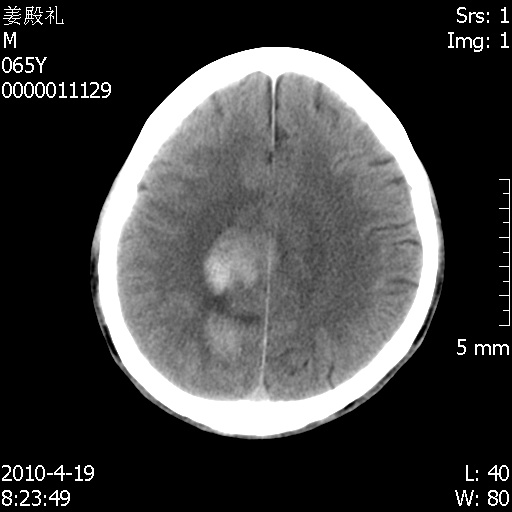

老年男性,突发左下肢无力1天,其余有价值的检查都没有。平扫ct值大约60hu,增强后ct值没什么改变,请大家讨论一下这个病例是什么?说明诊断理由。

左小脑、右大脑顶叶多发圆形高密度病灶,其周环状低密度影。考虑多发脑出血。隔期观察。

至于是出血还是微小钙化所致的高密度无法考证,三个都出血也不是一点都不可能,同一种组织学类型的肿瘤受到同一个外来的因素影响后会表现出相同的病理变化。说实在的,我本身支持转移瘤的,就是想不通为什么不强化?我认为单纯脑出血的边缘不会那么光滑,并且那也不是出血的常见部位,多发也不常见。

刚刚复习了转移瘤的不典型ct征象,有4条,分享给大家:

1、高密度灶:多为瘤内有较多沙粒体钙化所致,而不是出血,ct值可高达95hu;

2、无强化;

3、无水肿;

4、无占位效应。